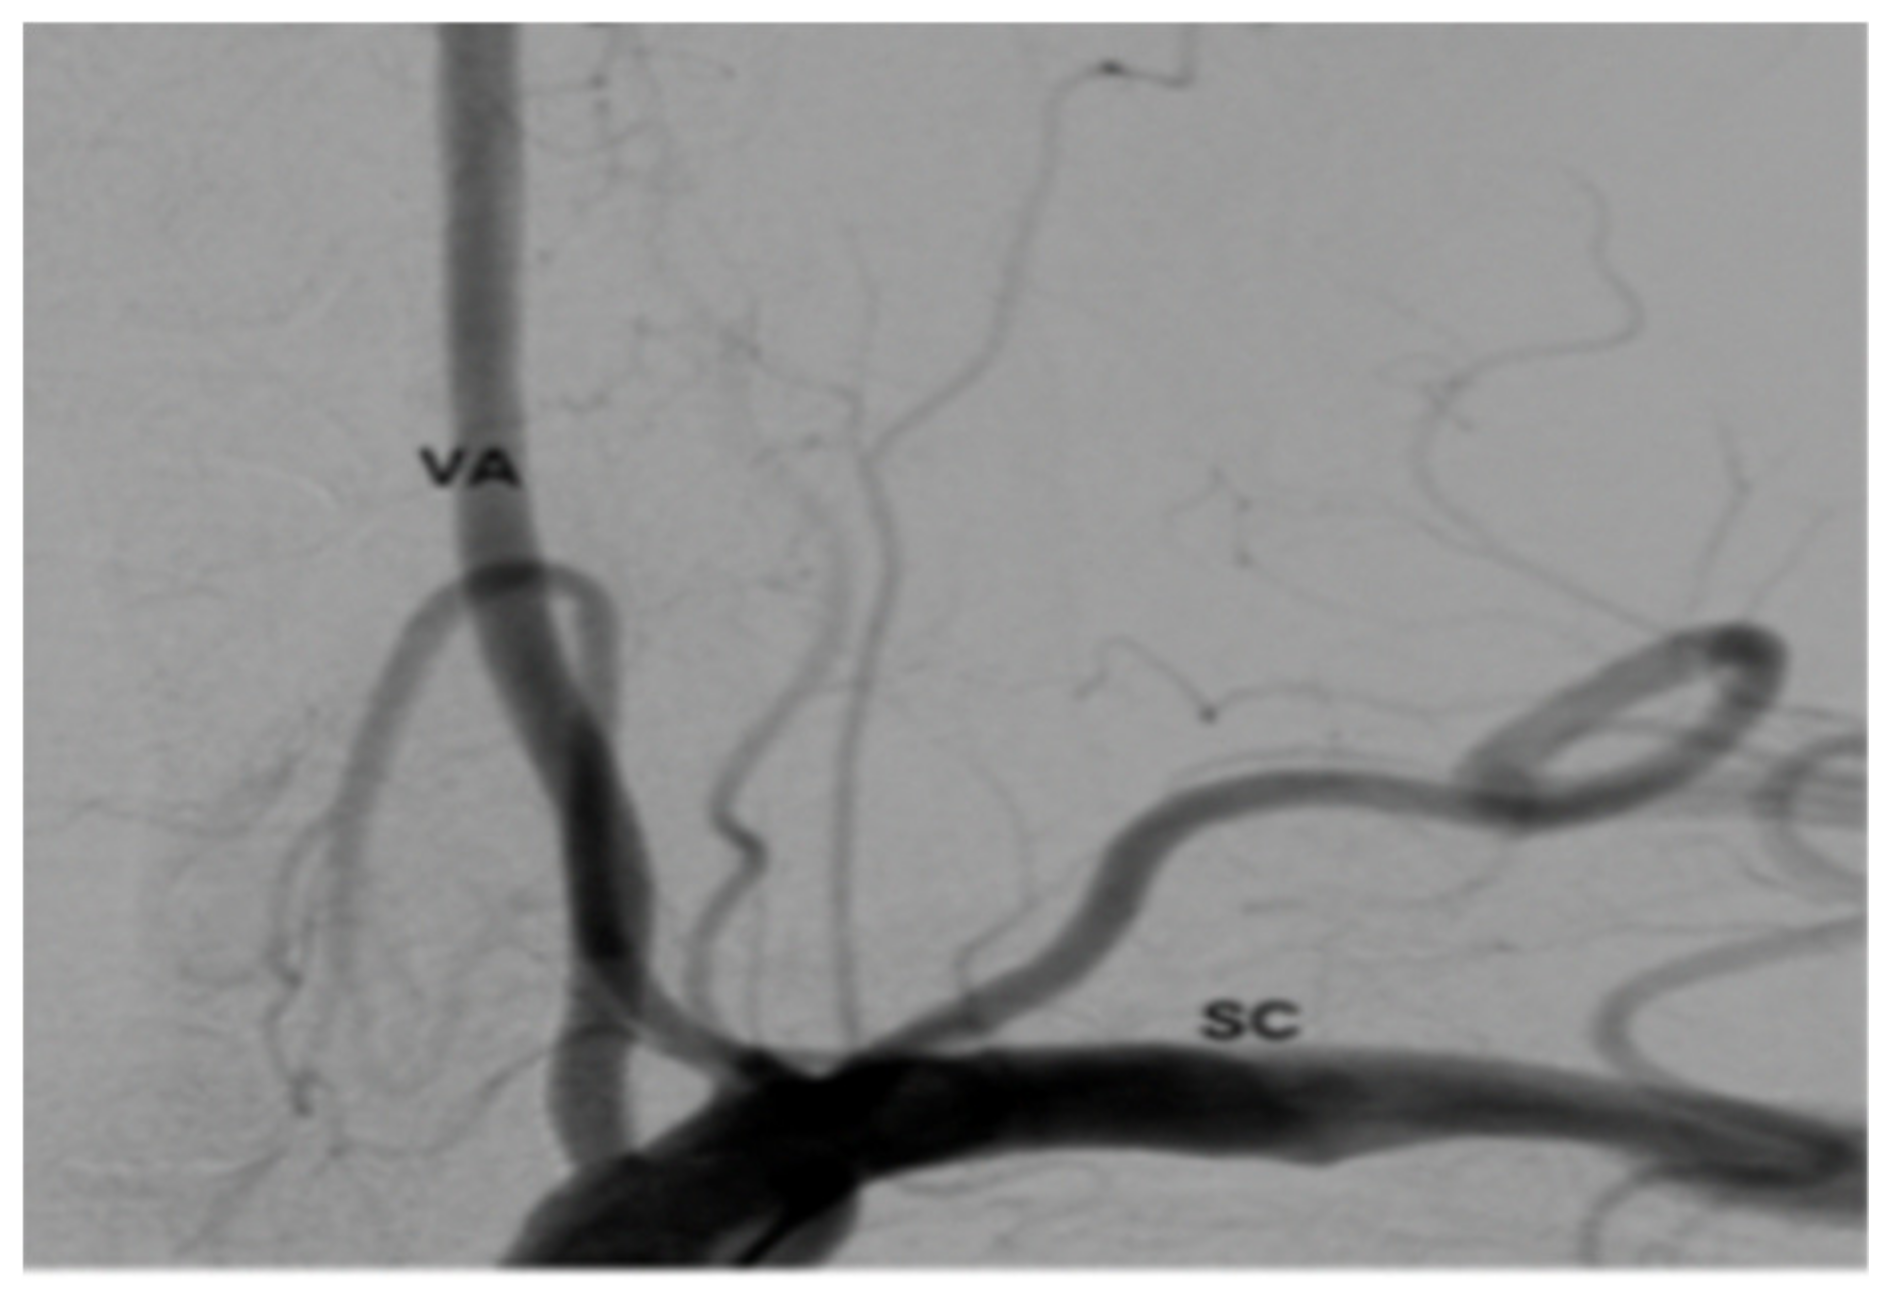

The patient was extubated and taken to the recovery room. Her blood pressure and pulse rate were within normal range. Her neurologic exam was intact with regard to mentation, coordination and motor function. Sensory deficits were unchanged from pre-operative exam. She was taken to the angiography suite and this revealed occlusion of the right VA (Figure 6). She had a contrast brain CT 48 h later, and no evidence of ischemia or infarct was noted. She subsequently was started on Aspirin (ASA) therapy on post-op day # 3. Serial exams throughout her 5-day hospitalization remained unchanged except for improvement in pre-operative sensory deficit. Follow up angiogram 6 months later showed recanalization of right VA (Figure 7).

Figure 6. Angiogram post-op.

Figure 7. Angiogram 6 months post-op.